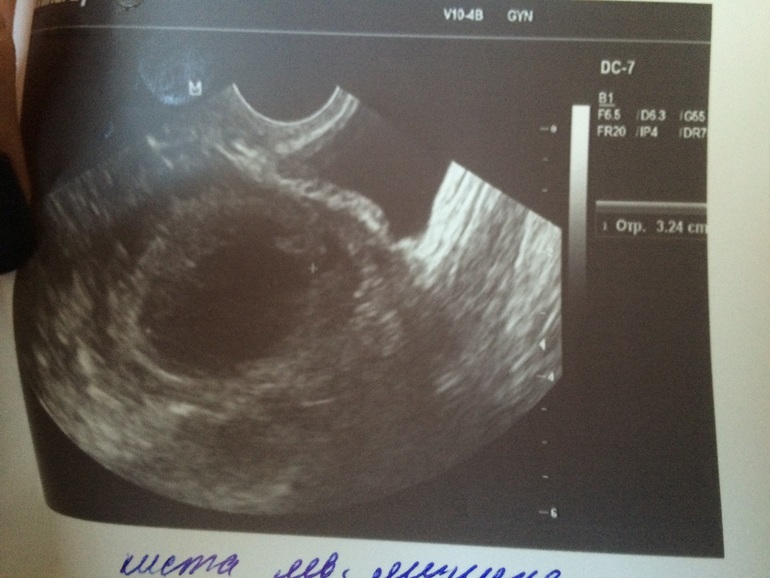

но так грустно стало что как узист говорит якобы перерос ДФ В КИСТУ фото под кат

так ли все плохо?((подскажите(

но вот меня смутило то что нет кровотока и жидкости